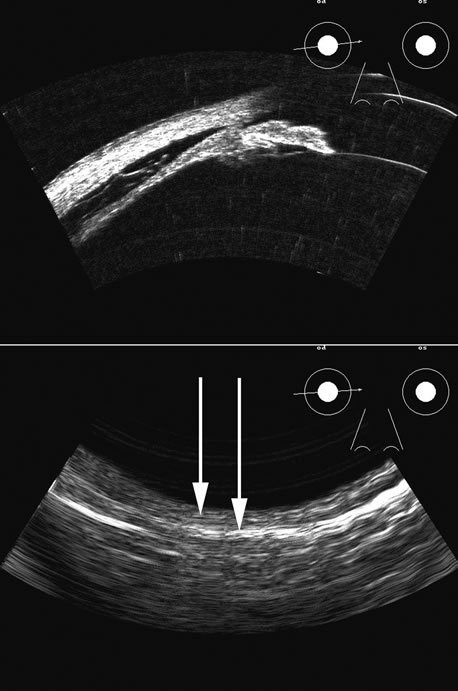

| The retina is a highly reflective surface (specular reflector) and

can be seen to always maintain its connection to the optic nerve, even

when drawn into an organized detachment. It may not be attached

at the ora serrata in giant tears, but otherwise it generally maintains

the two “landmark” attachments of optic nerve and ora serrata (Fig. 13), which can aid in differentiating the retina from the PLM of the

retracted vitreous and from the choroid, in which the detachment may

extend anterior to the ora and rarely extend back behind the vortex veins

to the nerve (Fig. 14).14 Two-dimensional scans through complex three-dimensional structures, such as preretinal membranes and proliferative membranes, can be confusing unless mapped with three-dimensional conceptualization techniques. Bronson and colleagues15 have emphasized three-dimensional thinking. Although new digital three-dimensional ultrasound systems allow direct volume visualization, it remains useful to understand the technique of conceptualizing three-dimensional structures from individual sections.16 Preretinal membranes (Fig. 15), which may resemble traction detachments in thickness and reflectivity, can often be identified by turning the scan plane of the B-scanner at right angles: the disciform retinal elevation is still seen while the linear nature of a traction sheet is revealed.17 A three-dimensional rendering of a retinal detachment can directly show the conformation of three-dimensional structures (Fig. 16), and images of individual planes can be perceived. Schisis can be difficult to differentiate from a peripheral detachment based on echo amplitude, but may be suspected based on location and other clinical factors, such as age and symptomatology. Schisis is usually convex and may have lower amplitude than a retinal echo. |